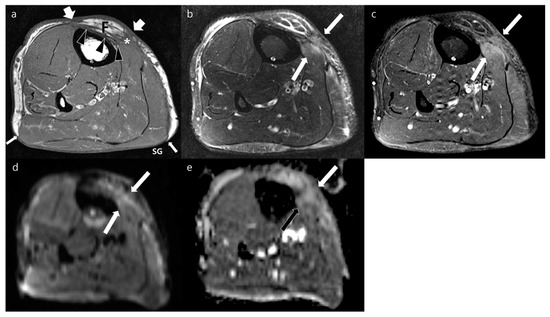

| Variables | Local Recurrences (n = 40) | Postoperative Changes (n = 36) | p Values | |

|---|---|---|---|---|

| Location on the transplanted soft tissue a | Peripheral margin | 25 | 22 | 0.907 |

| Deep margin | 11 | 12 | 0.583 | |

| Regional | 7 | 3 | 0.241 | |

| Border | Well-defined | 30 | 9 | <0.001 * |

| Ill-defined | 10 | 27 | ||

| Shape | Nodular | 39 | 20 | <0.001 * |

| Non-nodular | 1 | 16 | ||

| Size (cm) b | 2.6 ± 2.2 | 1.7 ± 1.0 | 0.020 * | |

| Sequences | Signal Intensity of MRI | Local Recurrences (n = 40) | Postoperative Changes (n = 36) | Hyperintensity vs. iso- or Hypointensity (p Value) |

| T1WI | Hyperintensity | 12 | 2 | 0.007 * |

| Isointensity | 26 | 31 | ||

| Hypointensity | 2 | 3 | ||

| T2WI | Hyperintensity | 34 | 15 | <0.001 * |

| Isointensity | 4 | 17 | ||

| Hypointensity | 2 | 4 | ||

| FS-T2WI | Hyperintensity | 38 | 27 | 0.020 * |

| Isointensity | 1 | 7 | ||

| Hypointensity | 1 | 2 | ||

| Contrast-enhanced FS-T1WI | Strong | 20 | 3 | <0.001 * |

| Moderate | 18 | 31 | ||

| Mild | 2 | 2 | ||

| DWI with high b-value | Hyperintensity | 37 | 30 | 0.294 |

| Isointensity | 1 | 4 | ||

| Hypointensity | 2 | 2 | ||

| ADC (μm2/s) a | 1297.0 ± 590.9 | 1634.6 ± 462.7 | 0.008 * | |

| Impeded water diffusion | Positive | 22 | 5 | <0.001 * |

| Negative | 18 | 31 | ||